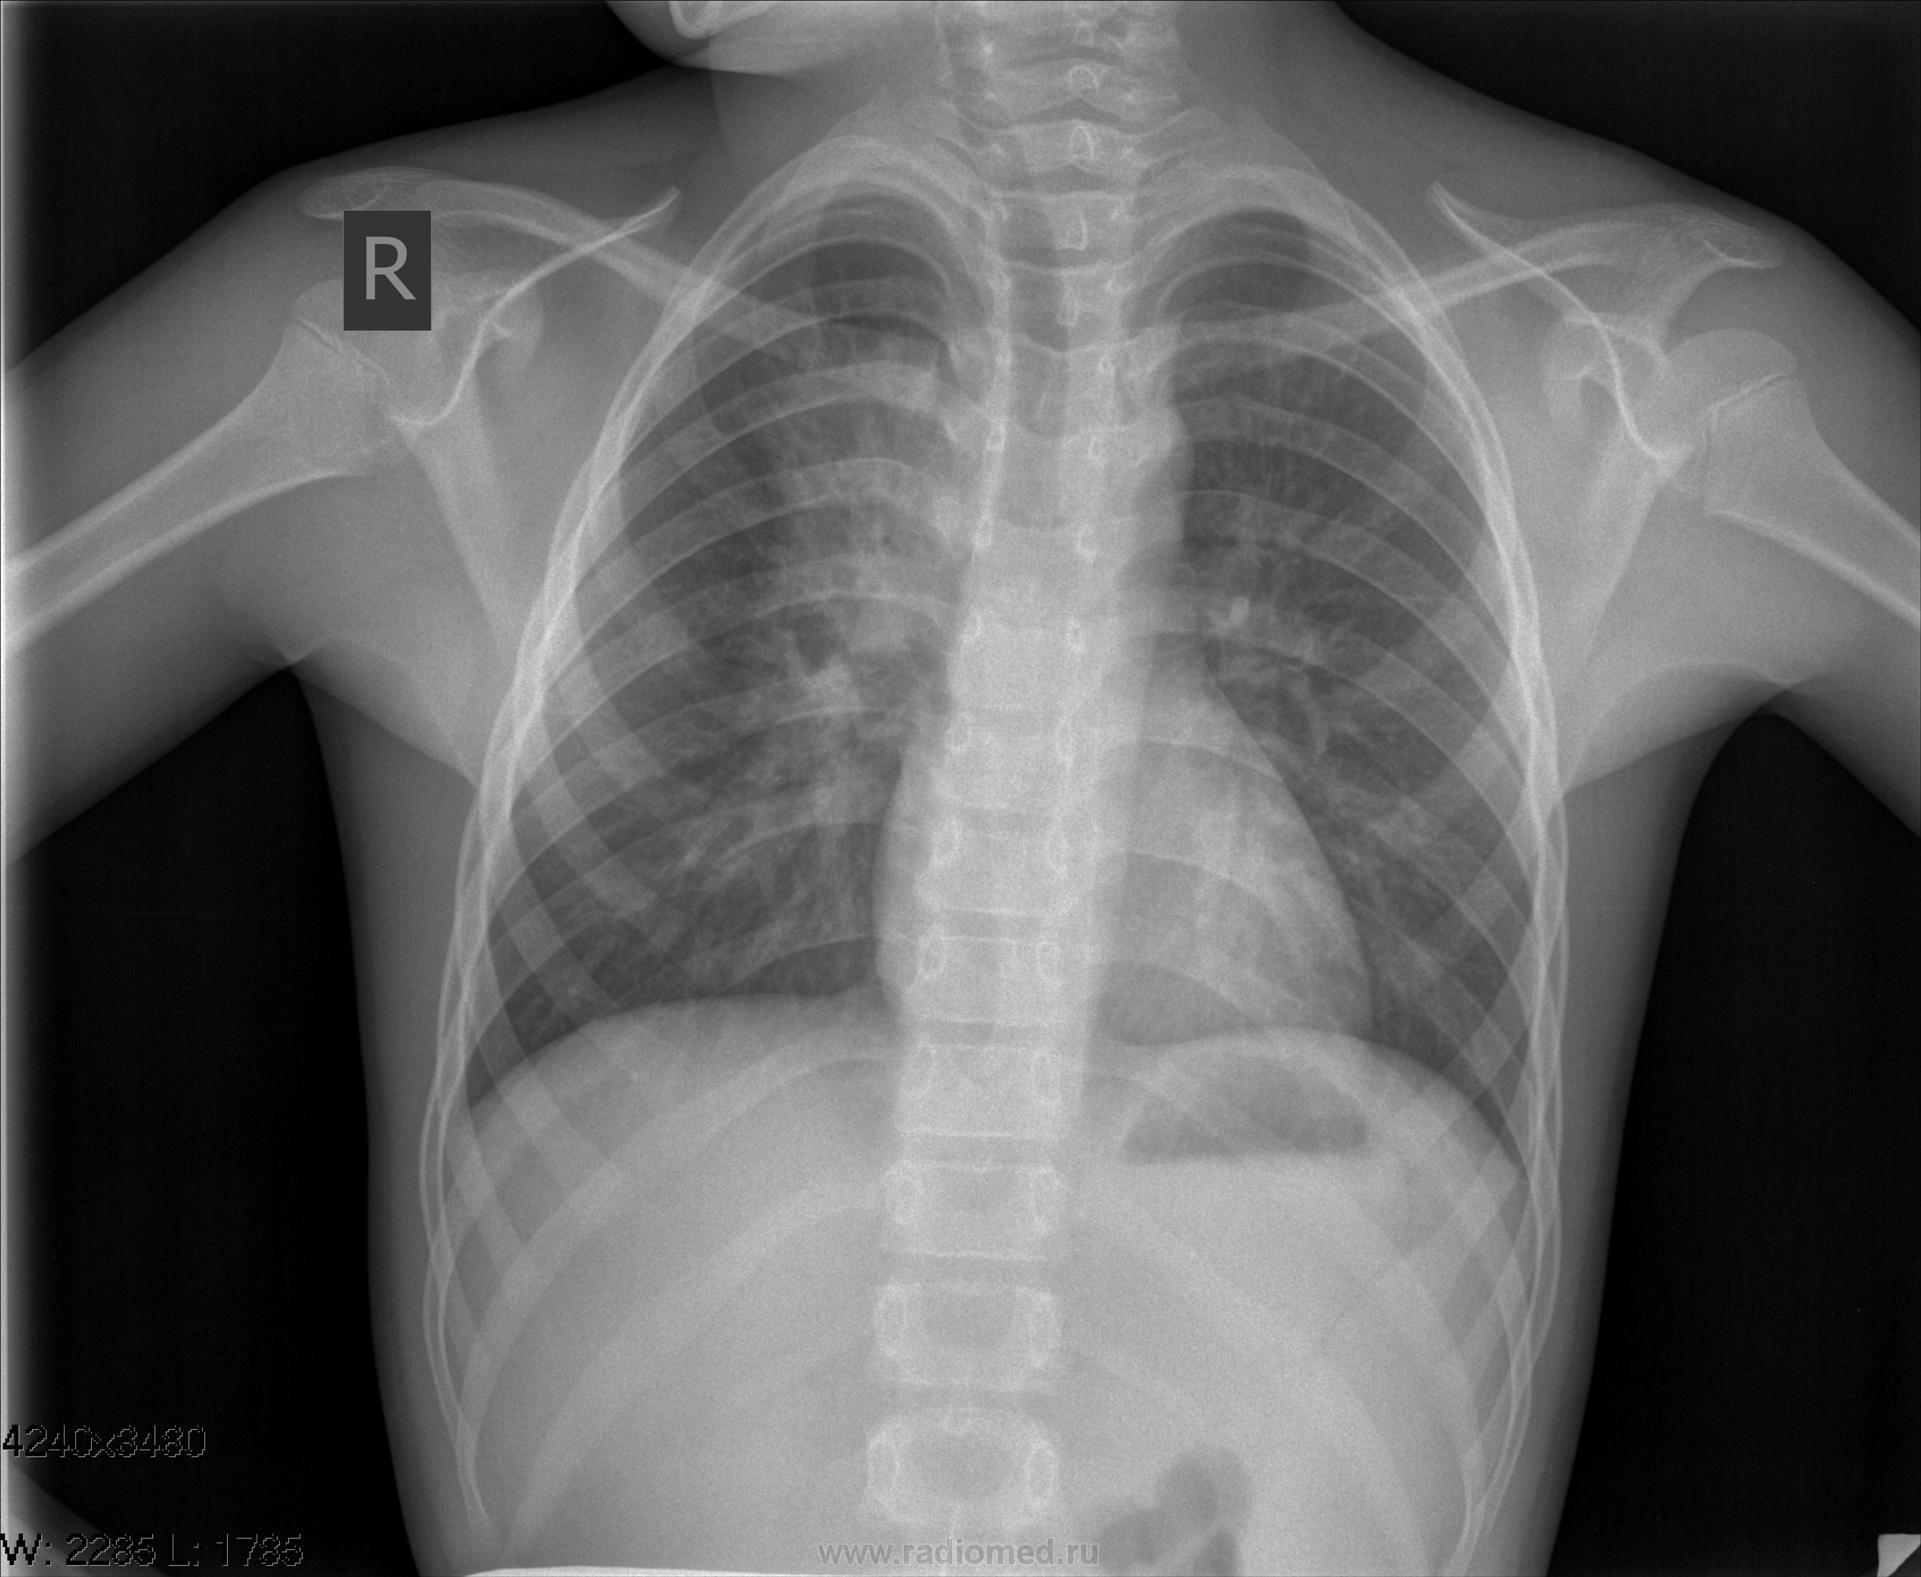

рентгенконтроль

ogk_3.jpgogk_4.jpg

Ну и все прекрасно, хорошо полечили пневмонию.

Не могу согласиться безоговорочно с необходимостью делать детям боковые снимки.  ( в смысле - всем подряд, где есть затенение). Назначаю  только,  если подозрение на деструкцию или ателектаз! Тогда, конечно, боковой совершенно необходим. Вот и этот случай, по-моему, показывает, что сначала - противовоспалительная терапия, динамика по клиническим показаниям.